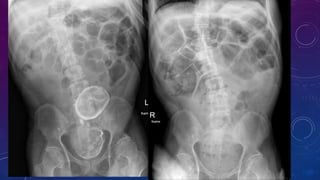

FAILED BILATERAL RENAL TRANSPLANTS

CALCIFICATION

WHERE?